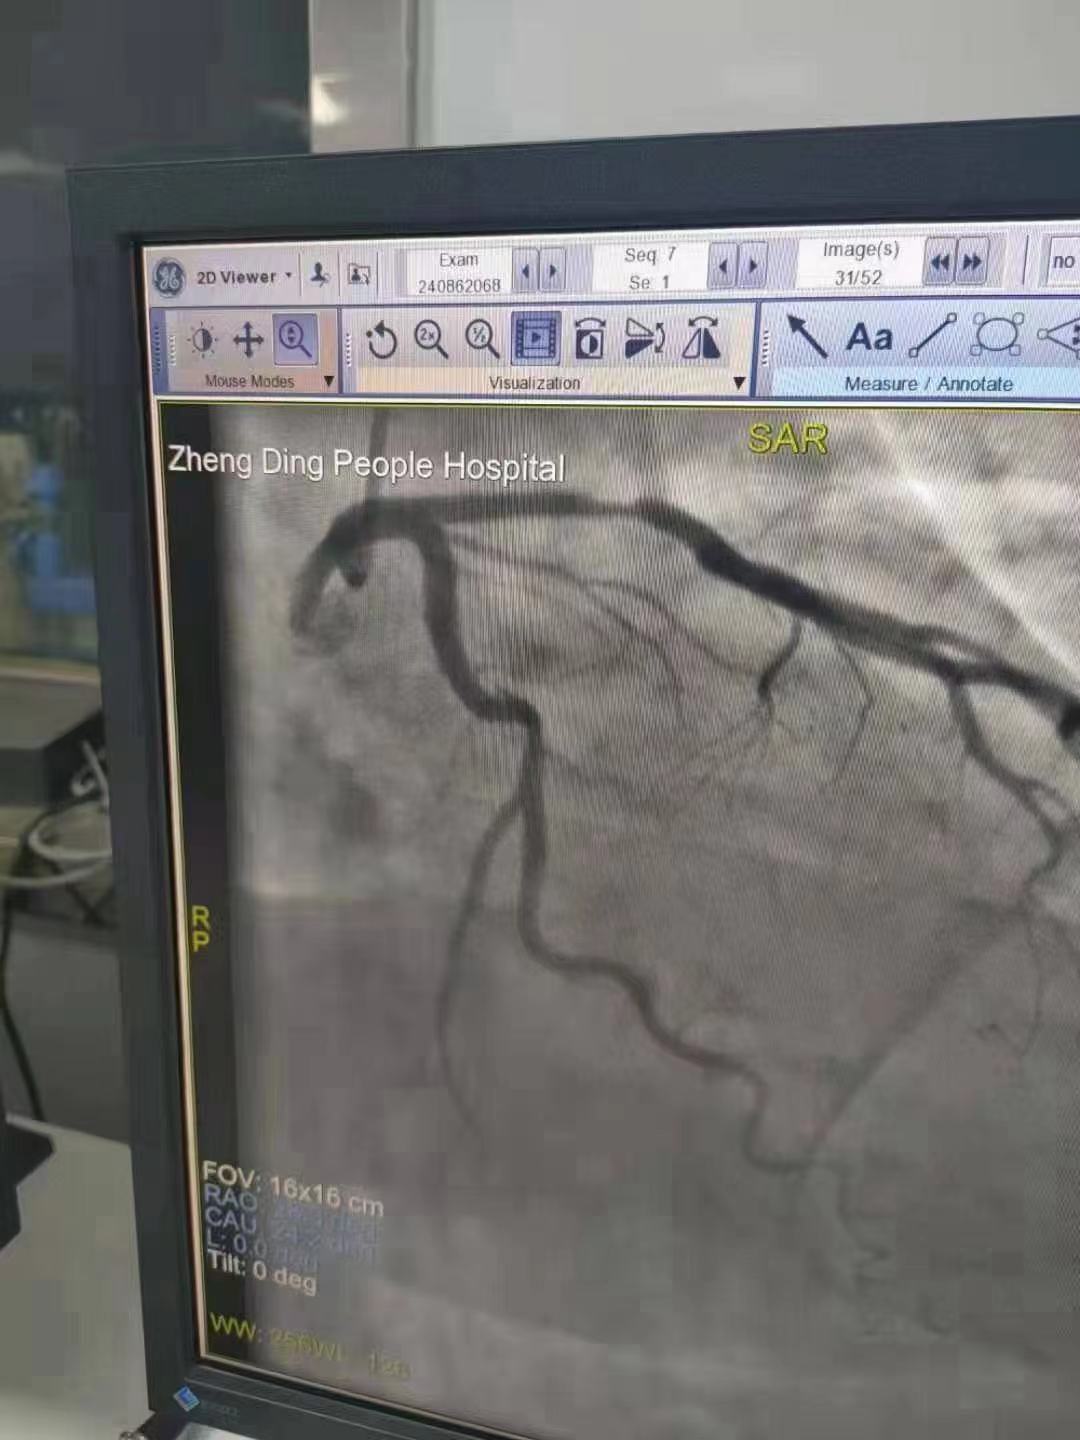

祝賀 正定縣醫(yī)院李京芳 主任團(tuán)隊(duì)成功為患者植入Xinsorb生物可吸收支架!